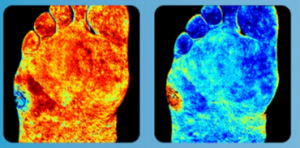

DIABETES CARE – MEDICAL DEVICE FOR TISSUE OXIMETRY

The Opportunity

Blackhawk Technologies, LLC is exclusively representing HyperMed Imaging Inc. (the“Company”) to monetize its’ assets related to a Medical Device for Tissue Oximetry for Diabetes Care. The offering includes an FDA cleared product used by clinicians and backed by 24 patent families comprising of 62 total assets.

Blackhawk Technologies, LLC is exclusively representing HyperMed Imaging Inc. (the“Company”) to monetize its’ assets related to a Medical Device for Tissue Oximetry for Diabetes Care. The offering includes an FDA cleared product used by clinicians and backed by 24 patent families comprising of 62 total assets.

The Company’s pioneering technology has been in service since 2006 and has been validated in third-party published papers that assessed oxyhemoglobin, deoxyhemoglobin, and oxyhemoglobin saturation in superficial tissue for diabetic patients. The Company’s FDA 510(k) cleared product, Hyper View™, quickly determines levels of oxyhemoglobin, deoxyhemoglobin and oxygen saturation in superficial tissue in a small and portable configuration.

The Company seeks a strategic acquirer/licensee with both resources and channels to fully commercialize Company’s IP assets.

The Unmet Medical Need

Most medical exams need quick and accurate determination of superficial tissue oxygenation. For example, complications in diabetes and/or peripheral arterial disease increases risk of lower limb ischemia, chronic wounds, amputation or even death.

• Over 420 million people worldwide (1 in 11 people) have diabetes and the number is increasing rapidly.

• More than 29 million Americans have diabetes. Another 86 million have prediabetes, which is 1 in 3 US adults.

• 8.5 million Americans have peripheral arterial disease and among them nearly 2 million people in the USA are living with limb loss.

• The main causes are vascular disease (54%), including diabetes and peripheral arterial disease.

• Approximately 185,000 amputations occur in the United States each year, costing over $8 billion.

• People with diabetes are at greater risk for severe peripheral arterial disease and are five times more likely to require an amputation.

• It is estimated that a low

Hyperspectral Imaging Benefits

• Non-contact color-coded images depicting concentrations of oxyhemoglobin & deoxyhemoglobin, and oxygen saturation without injectable contrast agents.

• Readings are predictive of wound healing and can be used in screening for peripheral vascular disease.

• Software tools allow clinicians to analyze specified areas within the image to localize ischemic tissue.

• Offers improved patient care with speed, ease of use, and clinical efficiency without injectable contrast or physical contact of the device with the patient.

• Safe, using visible light and spectrometer imaging to quantify light absorption in hemoglobin molecules for rapid analysis without leaving the exam room.

For more details about technology: Click Here